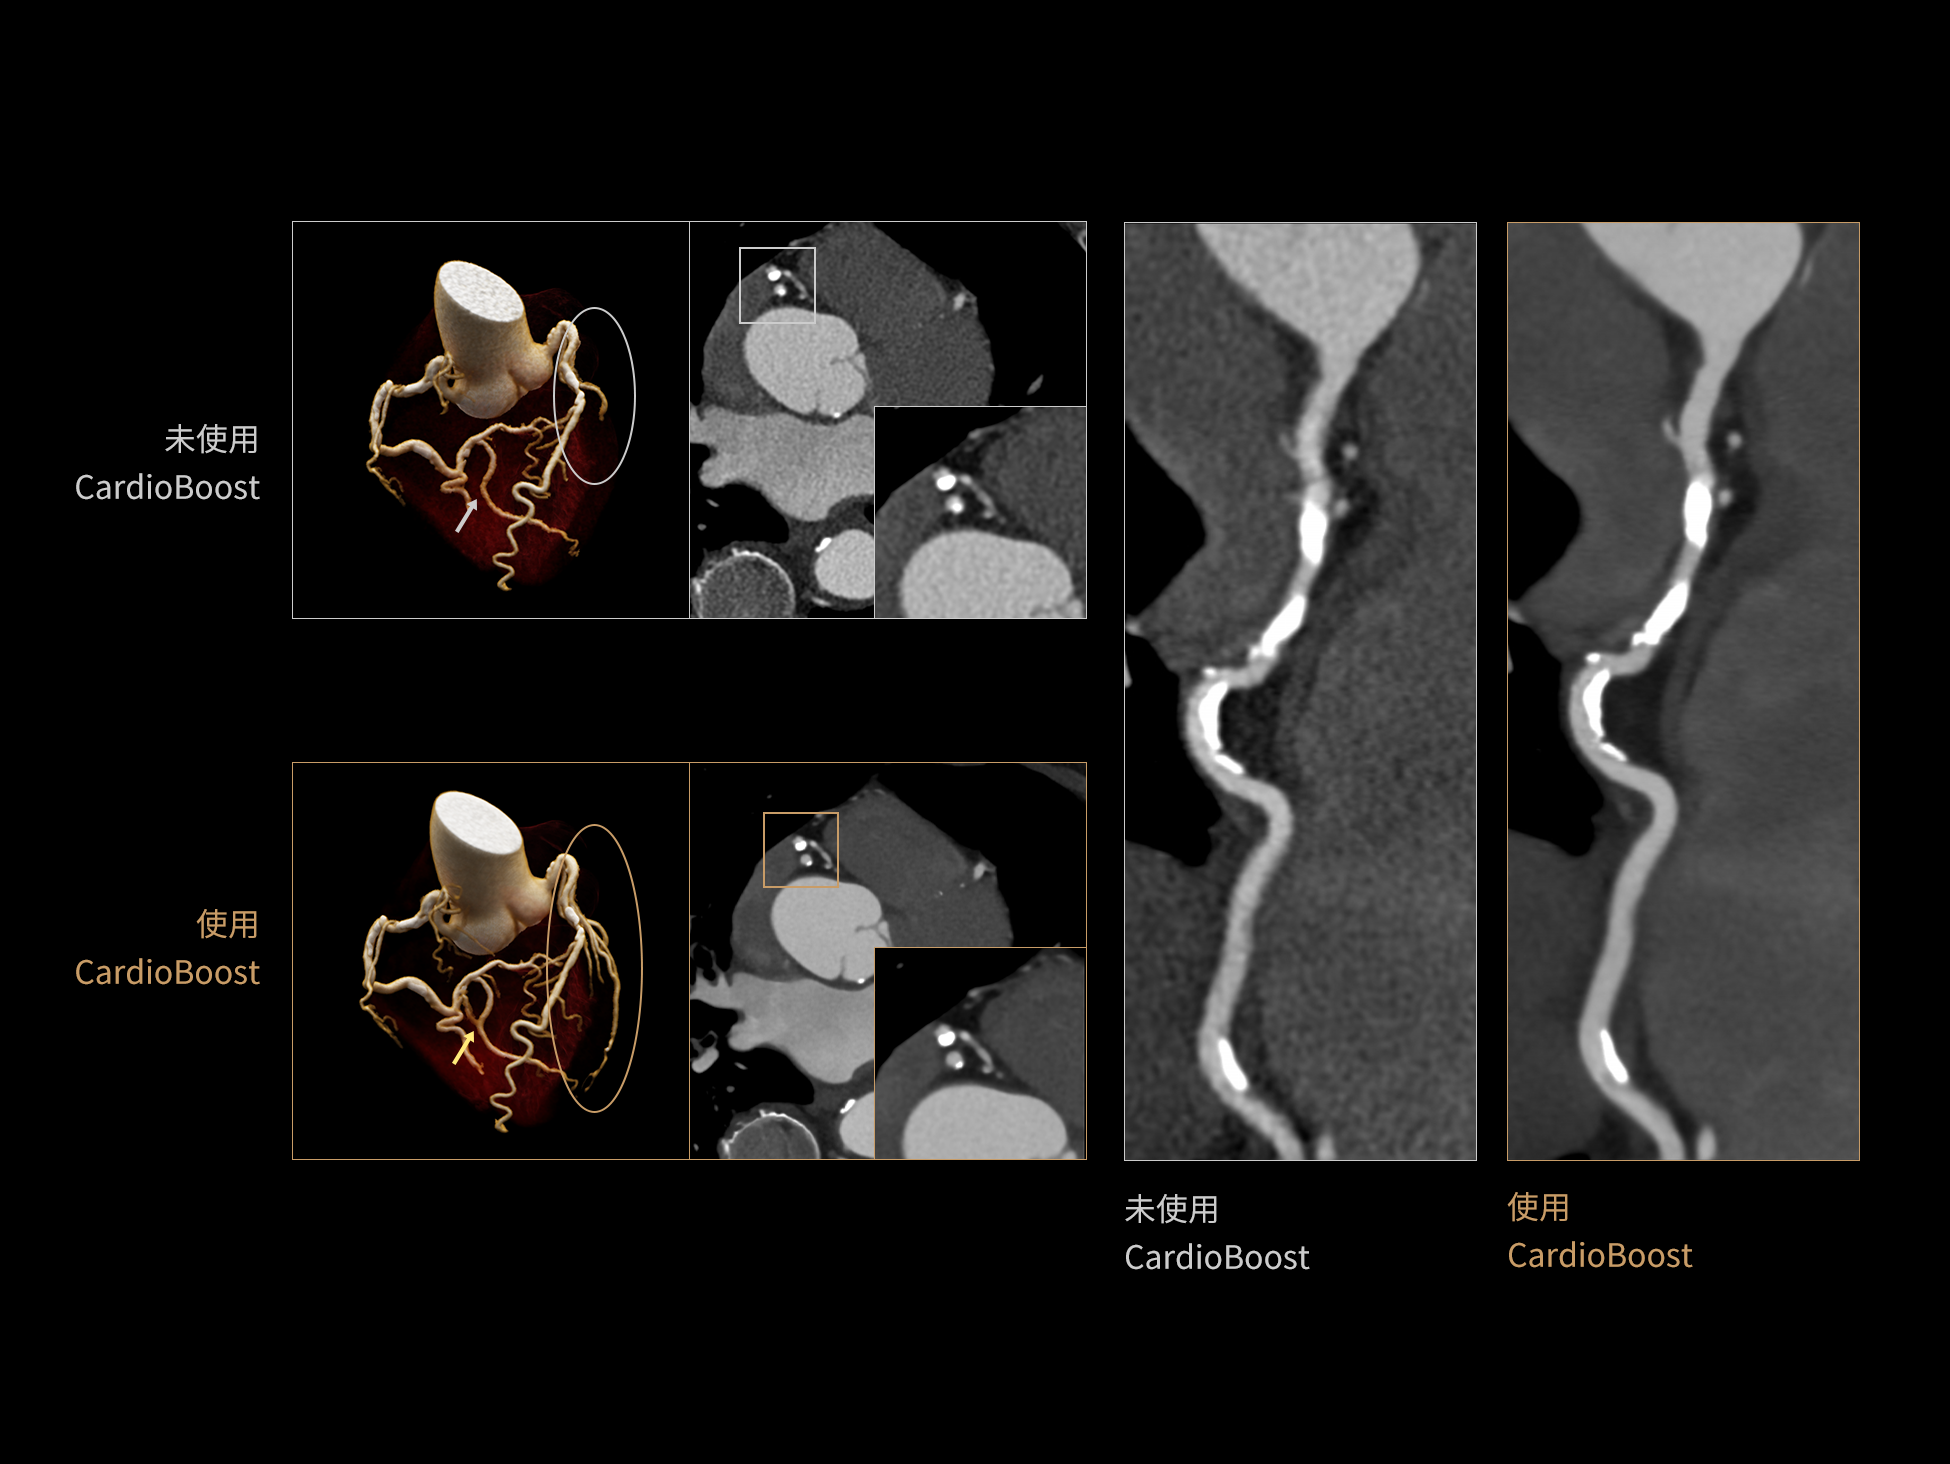

CardioCapture:AI冠脉运动追焦技术

CardioCapture 算法在冠脉运动伪影校正中采用全局化、系统化的处理策略。以目标时相为核心,重建多个相邻时相图像,利用深度学习技术提取连续时相中的冠脉树结构,构建时相间的运动模型,并对分段重建图像进行精准校正。通过这一过程,CardioCapture 可实现等效21 ms的超高时间分辨率,大幅提升冠脉图像清晰度与判读可靠性。

传统的血管提取通常基于CT值阈值和固定的冠状动脉模型,这种方法常常会失效,尤其是对于存在运动伪影的血管。 CardioCapture 算法基于深度学习网络,充分学习各类冠脉图像,以适应不同冠脉场景,精准高效完成冠脉及中心线提取,相较于仅基于CT 值和固定解剖模型的传统算法,CardioCapture 对于小血管及末端血管显示优势更加显著。

冠脉运动伪影校正过程

有效提取冠脉分支